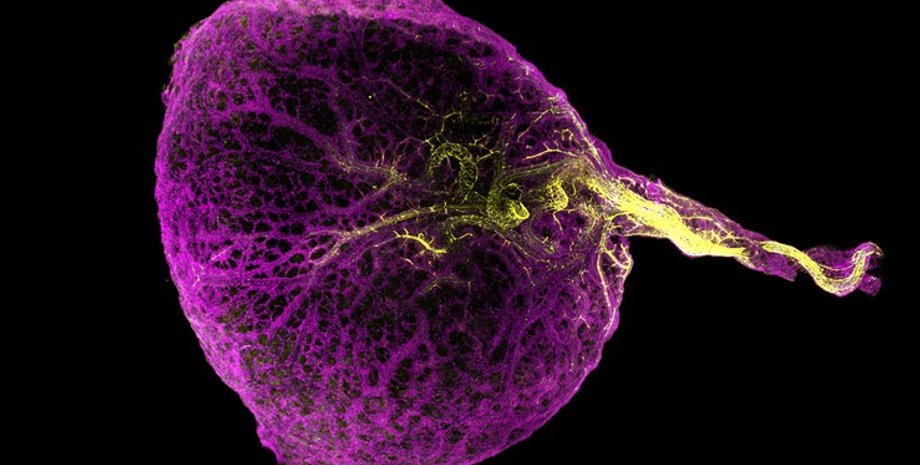

Людський жовтковий мішок (фіолетовий) із кровоносними судинами (жовтий) | Фото: Khoisan

Може здатися, що цей тимчасовий орган вельми даремний і є лише нагадуванням про наше далеке еволюційне минуле, але це зовсім не так.

До цього моменту його функції були незрозумілі дослідникам, а тому вони вважали, що цей тимчасовий орган, який атрофується до кінця першого триместру, не втримуючи жодної краплі їжі, а до 14 тижня й зовсім зникає, є еволюційним пережитком. У новому дослідженні, проведеному групою вчених на чолі з Інститутом Wellcome Sanger у Великій Британії, дослідники виявили відразу кілька важливих функцій, які він виконує.

Учені зазначають, що результати цього дослідження стали першими, які розкривають множинні органні функції жовткового мішка. По-перше, наш жовтковий мішок є джерелом наших найперших клітин крові. До того ж ідеться не тільки про червоні клітини, які транспортують кисень, а й про білі, що слугують імунною відповіддю. По-друге, вчені виявили, що ці клітини крові переміщуються з мішка в печінку, а потім у кістки, де й осідають, допомагаючи формувати кістковий мозок.